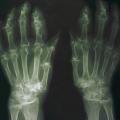

La forme pseudorhumatoïde est rare (5 %), simulant une polyarthrite rhumatoïde. L’arthrite chronique à PPC se présente comme une oligo- ou une polyarthrite, avec parfois des signes systémiques d’inflammation (élévation de la vitesse de sédimentation et de la protéine C-réactive [CRP]). La superposition d’accès aigus microcristallins est évocatrice de ce diagnostic. Il s’agit d’un diagnostic différentiel de polyarthrite rhumatoïde du sujet âgé ou de pseudopolyarthrite rhizomélique. Le diagnostic repose sur la mise en évidence des cristaux de PPC, même si les radiographies standard sont évocatrices. L’atteinte radiographique associe des calcifications des cartilages articulaires (fig. 7) et des fibrocartilages (fig. 8, 9, 10 et 11) [à rechercher systématiquement sur les radiographies de poignets, genoux et symphyse pubienne]. La mise en évidence d’une chondrocalcinose sur des radiographies standard renforce le diagnostic de rhumatisme à PPC mais l’absence de dépôts calciques ne l’élimine pas (la sensibilité de la radiographie standard étant imparfaite). L’échographie peut mettre en évidence des dépôts de PPC, qui apparaissent comme une fine bande hyperéchogène au sein des cartilages hyalins et comme des points scintillants dans les fibrocartilages ou dans la membrane synoviale. La sensibilité de l’échographie est bien supérieure à celle de la radiographie standard. Le scanner peut également mettre en évidence des dépôts calciques évocateurs, notamment au niveau du rachis ou du bassin qui sont plus difficilement explorés par les radiographies et l’échographie.